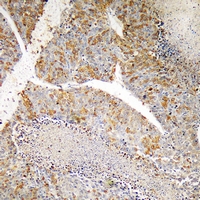

IHC (Immunohiostchemistry)

(Immunohistochemical analysis of PI3K p110 gamma staining in human liver cancer formalin fixed paraffin embedded tissue section. The section was pre-treated using heat mediated antigen retrieval with sodium citrate buffer (pH 6.0). The section was then incubated with the antibody at room temperature and detected using an HRP conjugated compact polymer system. DAB was used as the chromogen. The section was then counterstained with haematoxylin and mounted with DPX.)